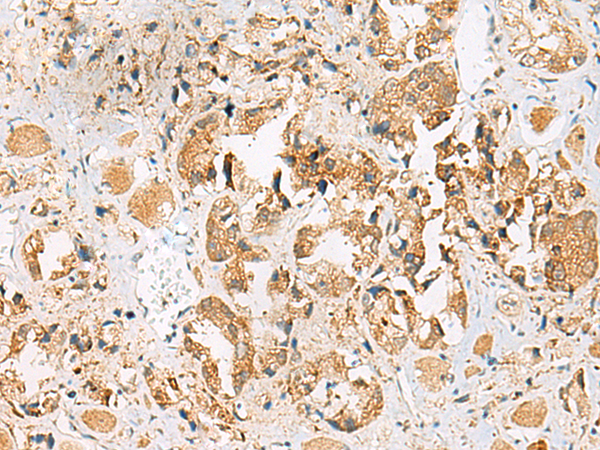

分类: 科研抗体货号: P13550别名: GSG2应用: IHC反应种属: Human